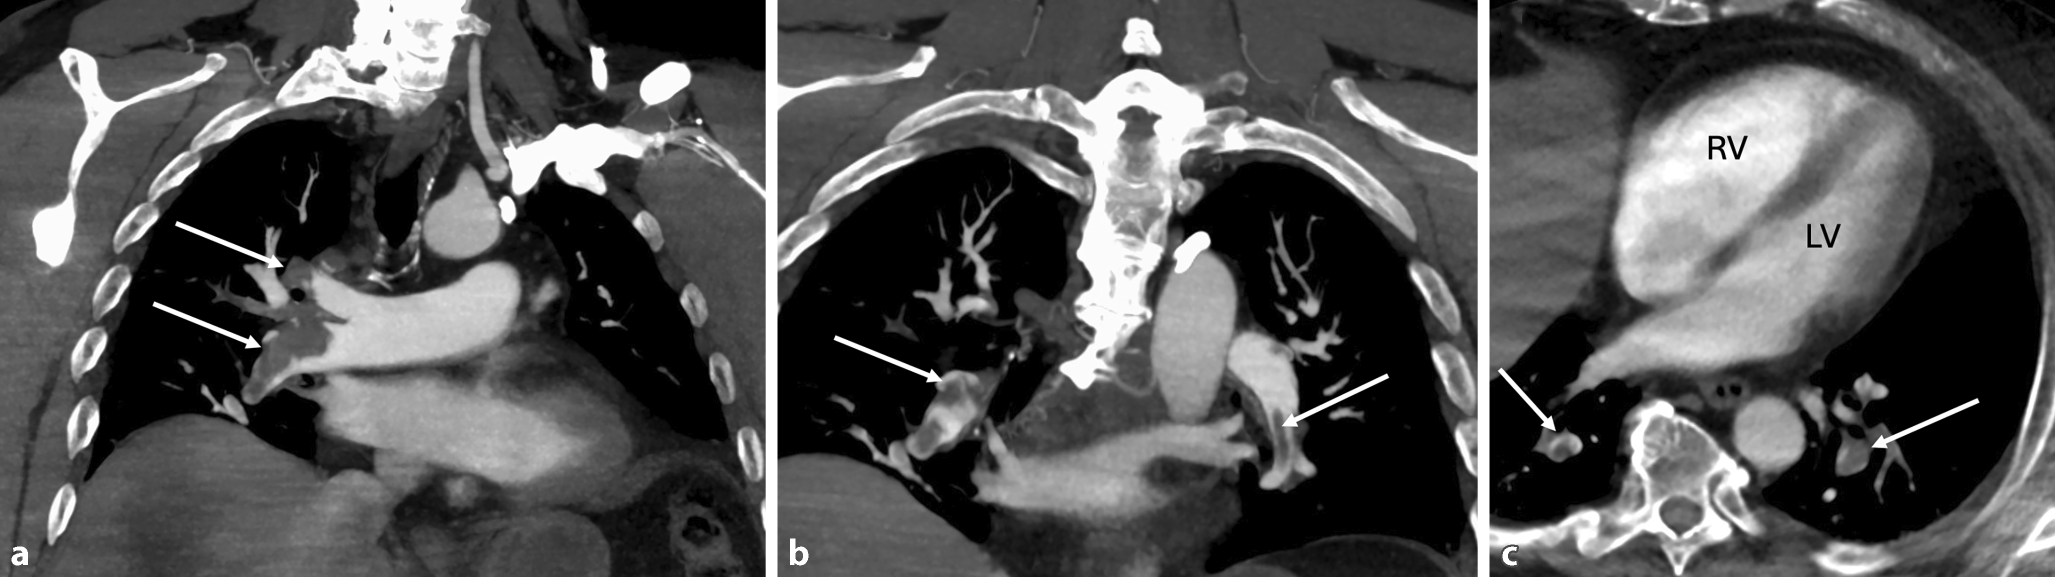

Das 12-Kanal-EKG ergab, bis auf eine Sinustachykardie, keinen wegweisenden Befund. Im Labor waren ein erhöhtes Troponin (153 ng/l, Normwert < 5 ng/l) und NT-proBNP (1250 pg/ml, Normwert < 125 pg/ml) auffällig. In der daraufhin erfolgten Echokardiographie ergaben sich Zeichen einer akuten Rechtsherzbelastung bei deutlich dilatiertem rechtem Ventrikel („RV/LV ratio“ 1,4) mit reduzierter Funktion (TAPSE 17 mm). In der danach durchgeführten CT des Thorax zeigte sich eine ausgeprägte zentrale Lungenembolie (LAE) mit hoher Thrombuslast (Abb. 1).

Abb. 1

CT des Thorax mit Kontrastmittel. a Darstellung der Lungenarterienembolie in der rechten Pulmonalarterie (Pfeil), b Darstellung der Lungenarterienembolie in der linken Pulmonalarterie (Pfeil), c Zeichen der Rechtsherzbelastung im CT bei im Verhältnis zum linken Ventrikel (LV) deutlich dilatiertem rechtem Ventrikel (RV). Periphere Thromben (Pfeil)